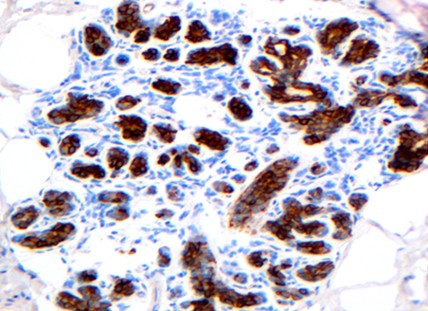

2.2 采用环保型GS组织样本制备套液制作的乳腺组织石蜡切片,经免疫组化P63和34βE12染色,结果显示,细胞内抗原成分保存良好,阳性结果定位准确,背景清晰,与传统方法制片染色效果基本相同(图2,3)。

图3乳腺腺病:腺上皮细胞胞浆34βE12(+)。PV-6000法×200